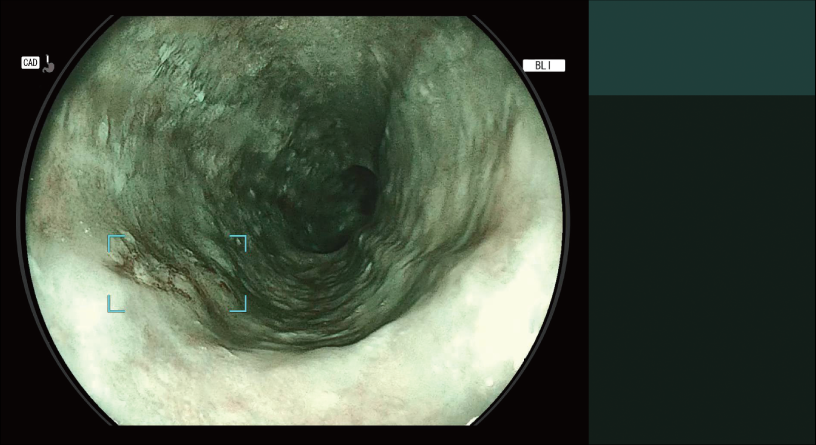

Detects the area that may be oesophageal squamous cell carcinoma and displays it on the main monitor in real-time.

Detection Box

Indicates the area where this software suspects that a lesion is present.

The types of Detection Mode are automatically switched depending on the observation mode selected.

- *2 Detection Mode for Oesophageal Squamous Cell Carcinoma Suspect Area